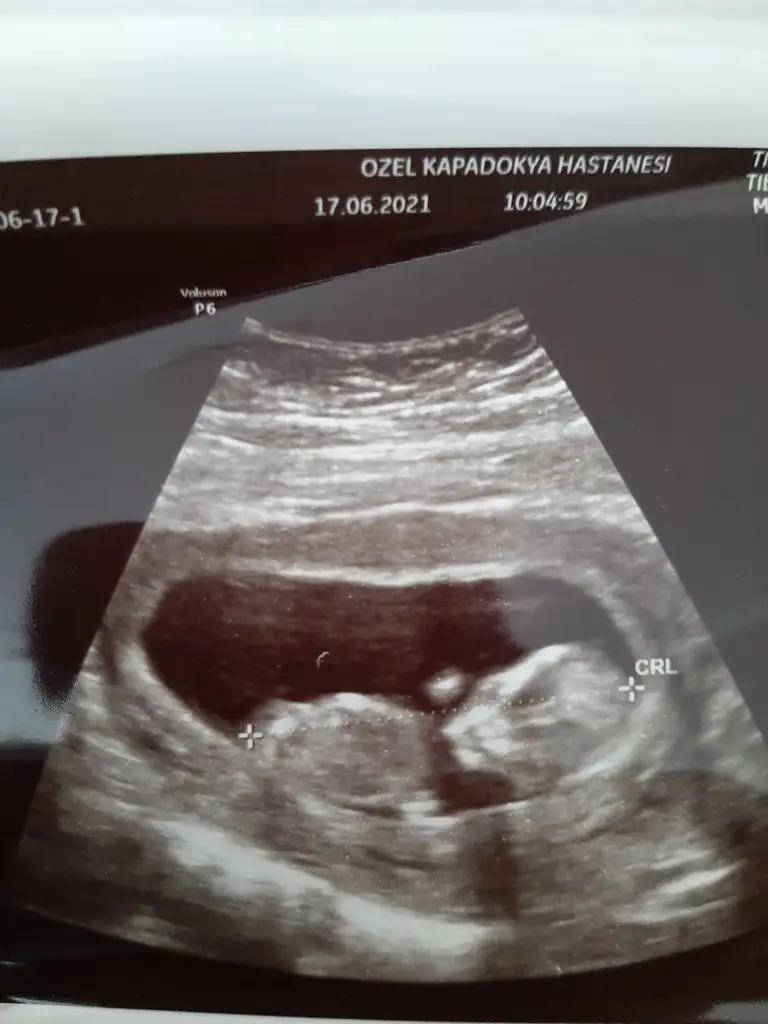

Bu ultrason görüntüsüne bakarmisiniz 🥰11+5di burda Ikra meyra Ikra meyra